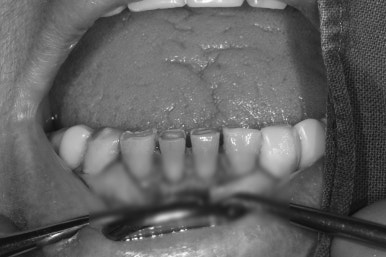

전체적으로 어금니가 여러개 없어요. 앞니는 깨졌어요.

처음 오셨을 때 촬영한 정면 구강 내 사진입니다.

위 앞니 보철물은 도재 (포세린,porcelain)가 깨져있어 보기 흉한 상태였고, 대부분의 어금니가 없으신 상황..

지금까지 어떻게 식사하셨을까요 ㅠㅠ

양옆으로 보았을 때도 아래 어금니는 모두 없어진 상태이고, 쓸수 있는 치아가 많지 않았어요.